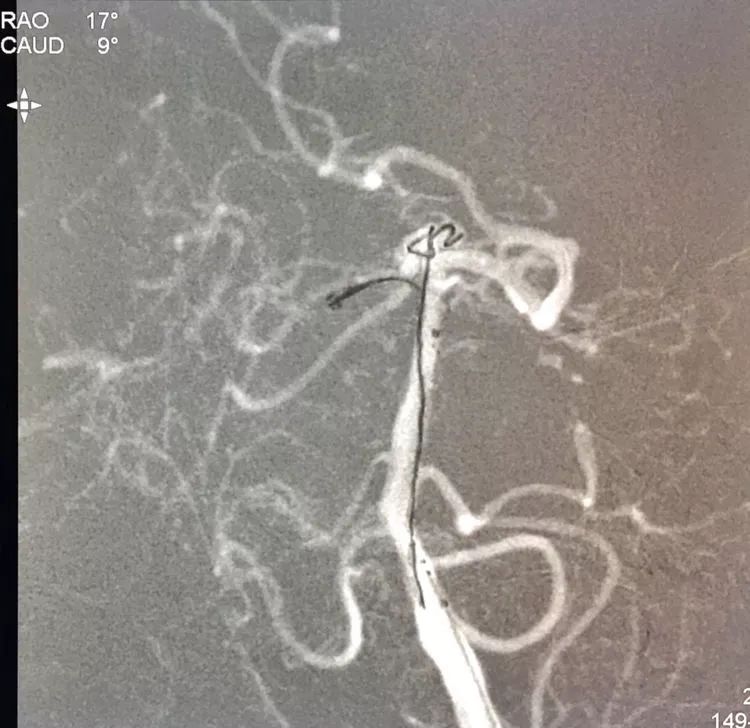

旋转增强器透视观察各个投照角度弹簧圈的分布情况,侧位透视发现瘤腔后部的弹簧圈分布疏松,形成死腔,看来革命还未成功,同志尚需努力呀!

回头再观察左椎动脉造影的三维成像,发现瘤腔确实有向后方突出的分叶,明确弹簧圈团后部的空虚处仍是瘤腔的一部分

此刻微导管的管头被支架压在瘤腔前部,显然无法再深入到瘤腔后部的死腔,这根直头的微导管该结束使命了,

换用一根新的Echelon10微导管,头端塑成C型,以Arvigo14微导丝引导(先前的Sychro14微导丝的头端已经有损了),经LVIS支架内部接近瘤腔后部的死腔,但微导丝可以进入死腔,微导管头死活钻不进去,被LVIS支架的网丝挡住去路,怎么办?那就隔着渔网袜挠痒!

微导管头顶在支架网眼处,投送一枚1.5-2的小圈,一开始弹簧圈走行入载瘤动脉(支架)内,用扭具调整弹簧圈头端的行进方向,并随之微调微导管头的方向和张力,圈终于成功钻入死腔!